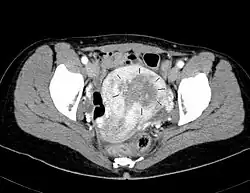

Symptome und Diagnose

Frühkarzinome können bereits vor dem Auftreten irregulärer Blutungen gelegentlich als Nebenbefunde im Abstrichmaterial bei der Früherkennung zum Gebärmutterhalskrebs entdeckt werden. Die bundesweite Statistik zählt für das Jahr 2015 etwas über 1.600 vorher unbekannte Endometriumkarzinome[14]; das entspricht 15 % der jährlich neu aufgetretenen Malignome. Außerdem macht sich der Tumor schon früh durch Blutungen bemerkbar. Eine Blutung nach Beginn der Menopause ist darum immer verdächtig, wie auch irreguläre Blutungen und fleischwasserfarbener Ausfluss. 75 % aller Endometriumkarzinome werden im ersten Stadium festgestellt.[15] Die 5-Jahres-Überlebensrate liegt dann bei 90 %. Unterleibsschmerzen bedeuten fast immer einen weit fortgeschrittenen, inoperablen Tumor. Die Diagnose wird durch eine Ausschabung der Gebärmutter (Abrasio uteri) gesichert.

In den letzten Jahren hat durch die 3-D-Sonographie die Diagnostik des Endometriumkarzinoms eine Verbesserung erfahren. Durch die Volumenmessung und durch die dreidimensionale Darstellung gelingt es, einerseits das Karzinom genau zu erkennen und andererseits die benignen Veränderungen zu erfassen. Hiermit können überflüssige Eingriffe in Form von Kürettagen vermieden werden. Derzeit sind ca. die Hälfte der Kürettagen vermeidbar.[16]